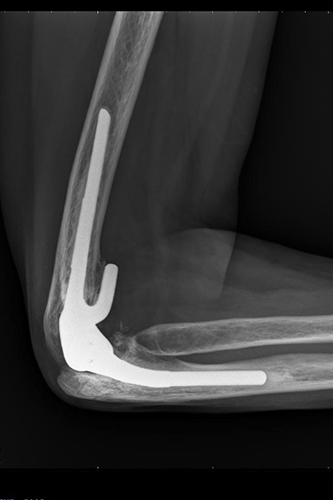

Nachher

Ellbogenröntgen seitlich

Ellbogengelenksendoprothese

2 Jahre nach der Operation